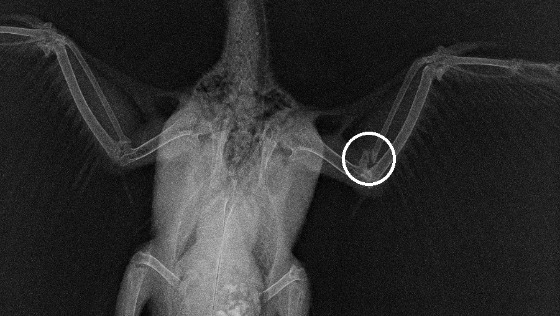

Po pół godzinie poszukiwań znalazła go 300 metrów dalej – niezły dystans jak na umierającego ptaka. Dziesięć minut zajęła pogoń za nim wśród stolików kwiaciarek i wielkich wazonów, ale udało się go schwytać. Ponieważ był to czwartek, więc ani lek. wet. Aleksandra Kornelia Maj, ani lek wet. Monika Toborek (dwie ptasie specjalistki) nie przyjmowały, zaniosła Benjamina (tymczasowe imię robocze) do najbliższej lecznicy. Okazało się, że Benjamin ma w wolu krew i ropę, na szczęście po oczyszczeniu wola był w stanie sam jeść, dostał też antybiotyk.

Następnego dnia lek. wet. Aleksandra Kornelia Maj zobaczyła, że gołębicy leci z dzioba tyle ropy, że znowu jest cała uświniona. Testy wykazały rzęsistka. Lekarka przepisała inne leki i kazała tuczyć na potęgę ten worek kości.